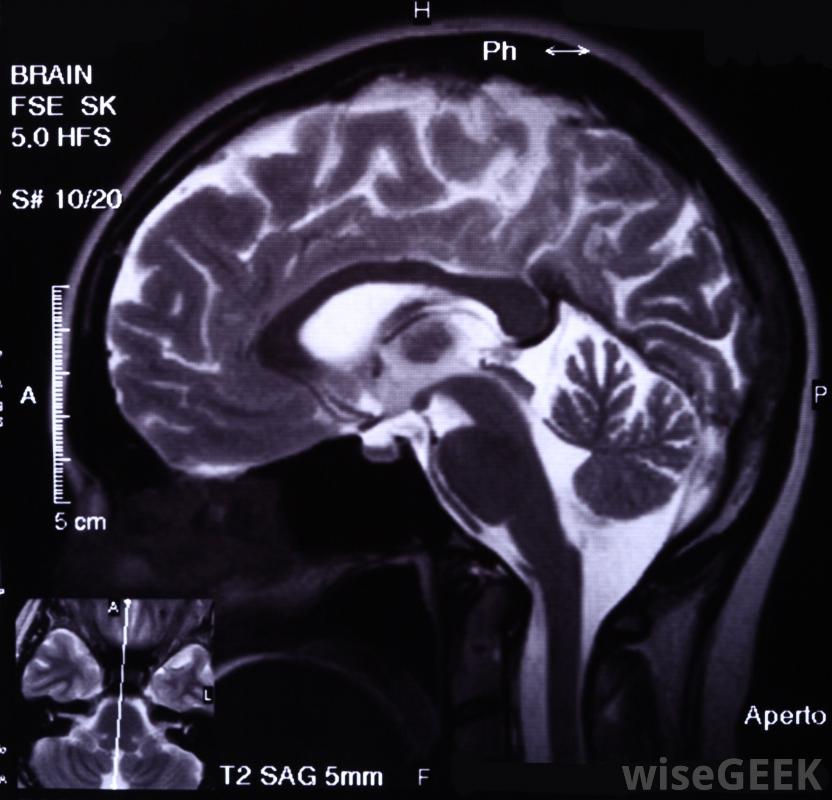

脑部扫描和脑电图可能会用于确定癫痫发作的原因。如果任何人看到某人有严重的mal,都可以遵循一些合理的急救步骤。患者应首先轻轻地将患者侧翻。这有助于防止防止呼吸道堵塞。然后,患者应准备一个枕头或卷起的毛巾或夹克,并将其放在受害者头部下方。